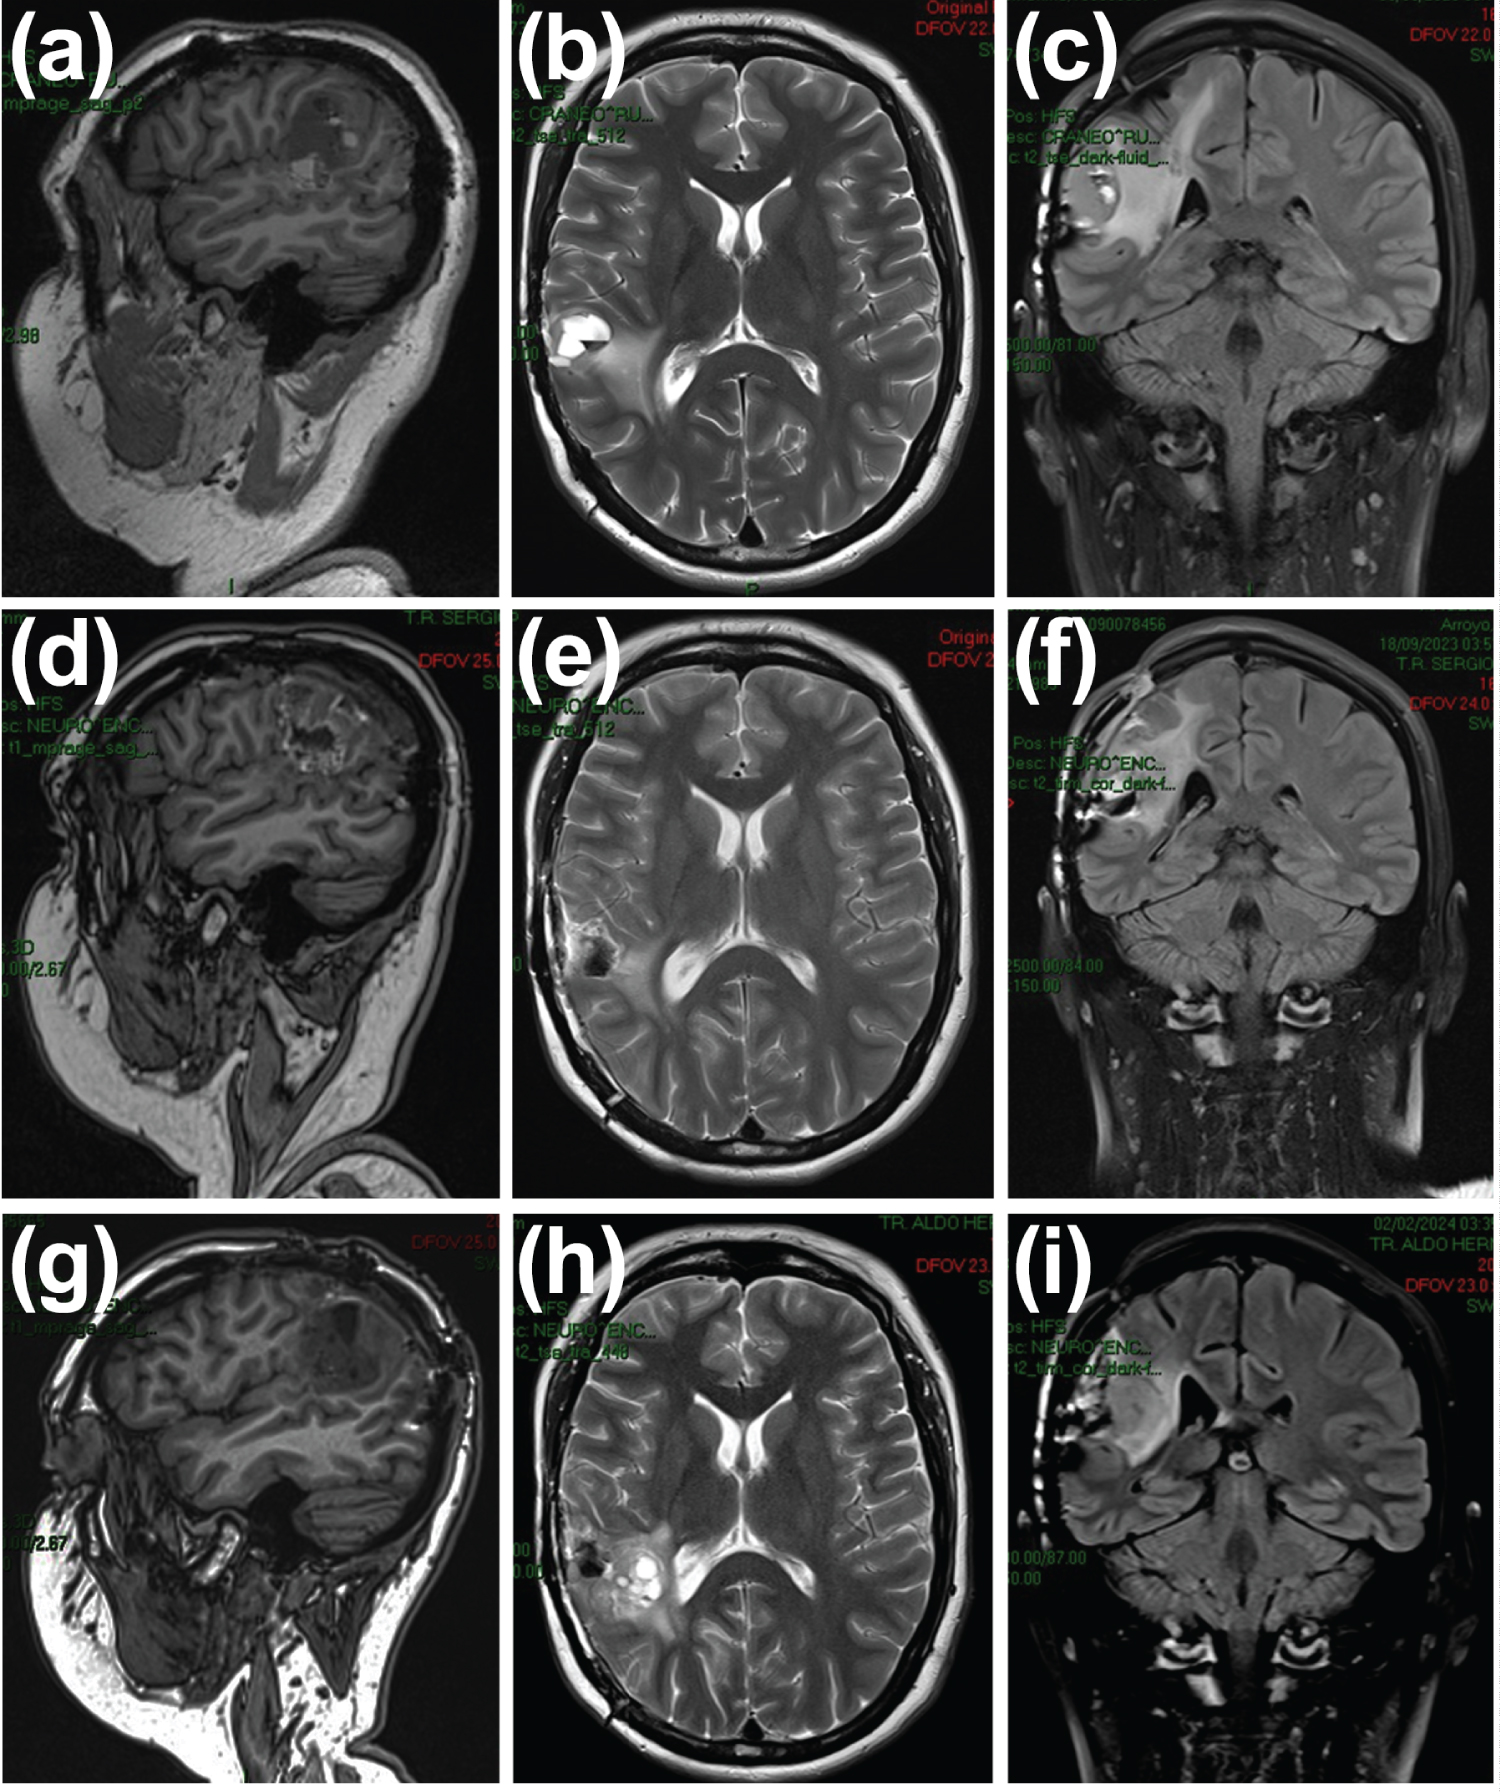

The MRI conducted in May 2023, prior to nanoparticle placement (Figure 4A, Figure 4B and Figure 4C), revealed a hyperintense image in the correct surgical bed, involving the posterior region of the insula, superior temporal gyrus, and supramarginal gyrus, evident in the T2 and Flair pulse sequences. This area appeared hypointense in T1, with focal areas of hyperintensity suggestive of methemoglobin, alongside haemosiderin deposits both internally and peripherally, as well as images displaying a liquid-liquid level. The described image measured 2.1 × 2.2 cm in the axial plane, 2 × 2.2 cm in the coronal plane, and 2.3 × 2.3 cm in the sagittal plane, showing intense enhancement with contrast medium. Additionally, peripheral hyperintensity was observed in the T2 and Flair pulse sequences between the surgical bed and the lateral ventricle wall, atrium, and corresponding superior temporal gyrus. Increased thickness of cerebral gyri, with mass effect on those corresponding to the dorsal region of the insula, was noted, along with obliteration of adjacent subarachnoid spaces. Haemosiderin deposits were also identified in the posterior frontoparietal region. Notably, increased mean transit time and cerebral blood volume were observed at the neurosurgical site during the perfusion phase.

Figure 4: MRI of the cerebellum. May 2023. a) Sagittal section in T1 sequence; b) Axial section in T2 sequence; c) Coronal section in T2 FLAIR sequence. September 2024; d) Sagittal section in T1 sequence; e) Axial section in T2 sequence; f) Coronal section in T2 FLAIR sequence. February 2024; g) Sagittal section in T1 sequence; h) Axial section in T2 sequence; i) Coronal section in T2 FLAIR sequence. View Figure 4

Following the placement of ultra-nanoparticles, a control MRI was performed in September 2023 (Figure 4D, Figure 4E and Figure 4F), revealing surgical changes due to tumor resection at the right frontotemporal level. A hematoma of the surgical bed with axial axes measuring 2.9 cm × 2.2 cm was observed in the axial plane, displaying heterogeneously high signal intensity in T2-weighted sequences, with a hyperintense halo in pre-contrast T1 sequences and discrete peripheral enhancement post-contrast medium administration. Perilesional edema persisted, involving the subcortical and deep white matter of the right precentral gyrus, semiovale center, and ipsilateral superior temporal gyrus, albeit decreased compared to the previous study. Increased signal was noted within the ventricles and extra-axial space in the subarachnoid space between the sulci and fissures of the right parietal lobe adjacent to the surgical site, suggesting the presence of ultra-nanoparticles. Additionally, a laminar subdural collection measuring 5 mm thick was identified adjacent to the craniotomy site. Consequently, the medical committee decided to infiltrate the bionanocatalyst (ultra-NPt) given the recurrent nature of the tumor, with the expectation of complete tumor disappearance.

In February 2024, another control MRI was conducted, revealing discrete dilatation of the lateral ventricle and right atrium due to secondary traction (Figure 4G, Figure 4H and Figure 4I). The surgical bed exhibited approximate dimensions in the sagittal plane of 43 × 35 mm (previously 37 × 27 mm), coronal plane 42 × 31 mm (previously 40 × 17 mm), and axial 34 × 34 mm (previously 25 × 27 mm). Its signal intensity appeared heterogeneous, attributed to multiple cystic areas of varying dimensions surrounded by corticocortical hyperintensity indicating edema. This edema extended to the superior temporal gyrus, periventricular region, and dorsal aspect of the insula, involving the semioval center, pre- and postcentral gyrus, and the lateral margin of the corpus callosum. Notably, the cerebral gyri corresponding to the third and fourth frontal gyri and the parietal lobe exhibited increased volume, with local subarachnoid spaces obliterated. Signal intensity restriction areas were observed within and medial to the surgical site, alongside identified haemosiderin deposits.